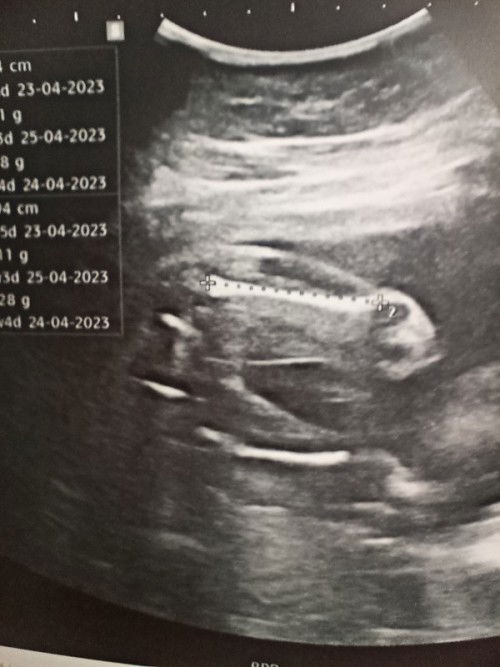

ช่วยดูเพศลูกหน่อยค่ะ

แบบนี้เพศอะไรคะ ใช่ผู้หญิงไหม ช่วยดูหน่อยค่ะ 👶🏻❤️ #ขอบคุณสำหรับคำตอบค่ะ